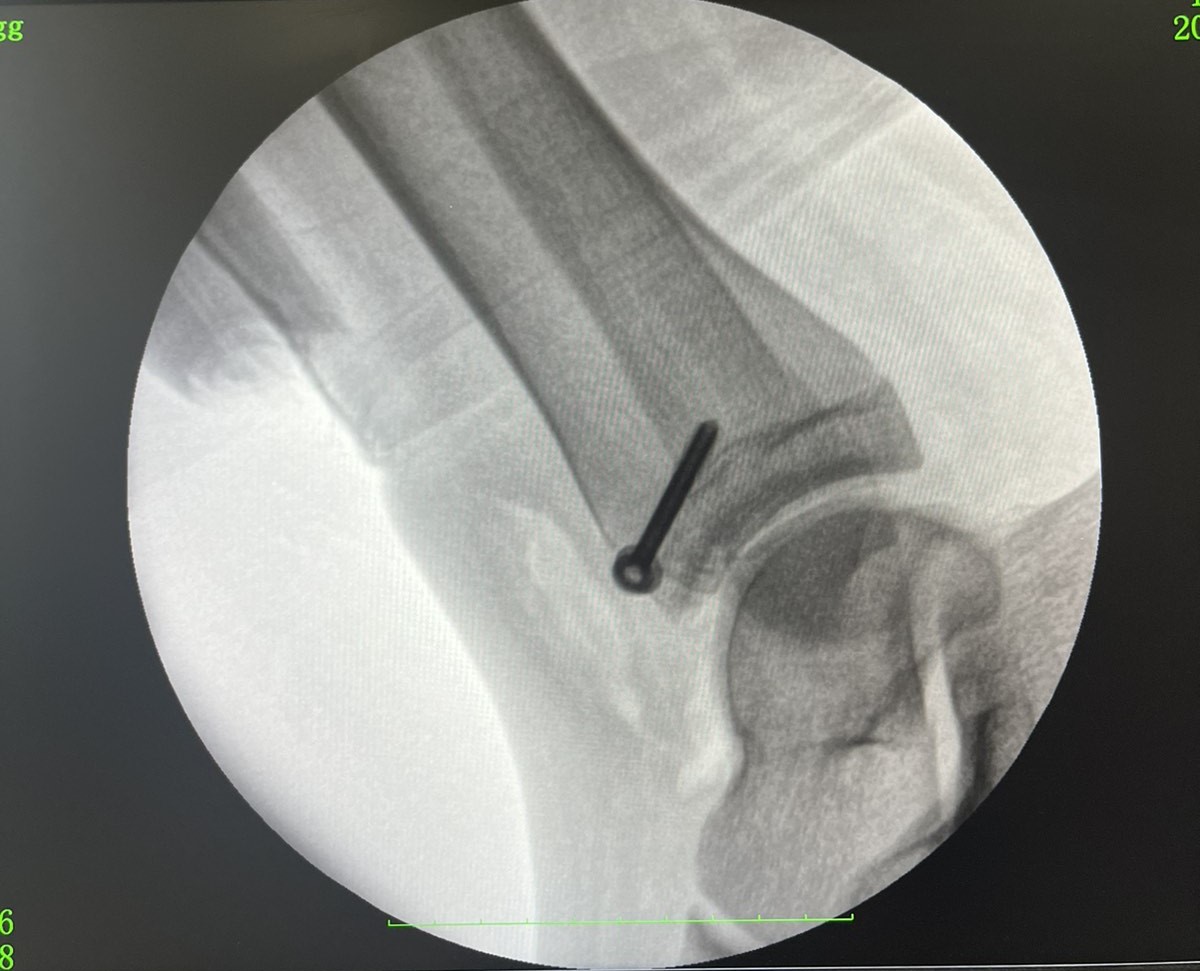

Перелом Тилло (фото: facebook.com/RivneODL)

Отмечается, что для лечения перелома Тилло используется методика открытой репозиции и фиксации титановым винтом. После операции полное восстановление функции голеностопного сустава занимает от 6 до 12 месяцев.

По словам медиков, этот вид перелома возникает вследствие излишней наружной ротации в голеностопном суставе. Он приводит не только к деформации кости, но и к повреждению передне-нижней большеберцовой связки.